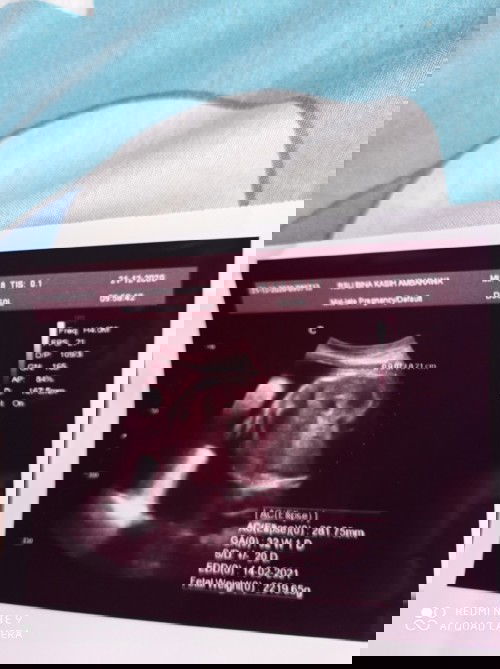

Lingkar perut (AC) : 281,75 GA ( usia kehamilan ) : 32 minggu 1 hari Edd ( hpl ) : 14- feb-21 Fetal weight : 2219 gram